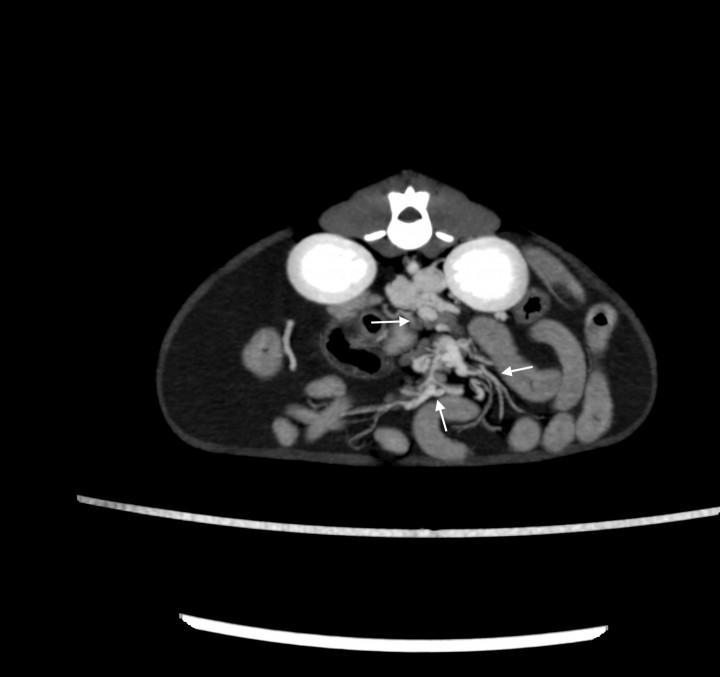

<p>Imagen tomográfica transversal tras la administración de contraste intravenoso, ventana de tejido blando y con proyección de máxima intensidad (MIP) con sumatorio de cortes. Se observan múltiples vasos tortuosos a nivel del abdomen central (flechas).</p>

Figura 11

Imagen tomográfica transversal tras la administración de contraste intravenoso, ventana de tejido blando y con proyección de máxima intensidad (MIP) con sumatorio de cortes. Se observan múltiples vasos tortuosos a nivel del abdomen central (flechas).

- Múltiples vasos tortuosos a nivel del abdomen central distribuidos por el resto del peritoneo de difícil caracterización (Fig. 11).